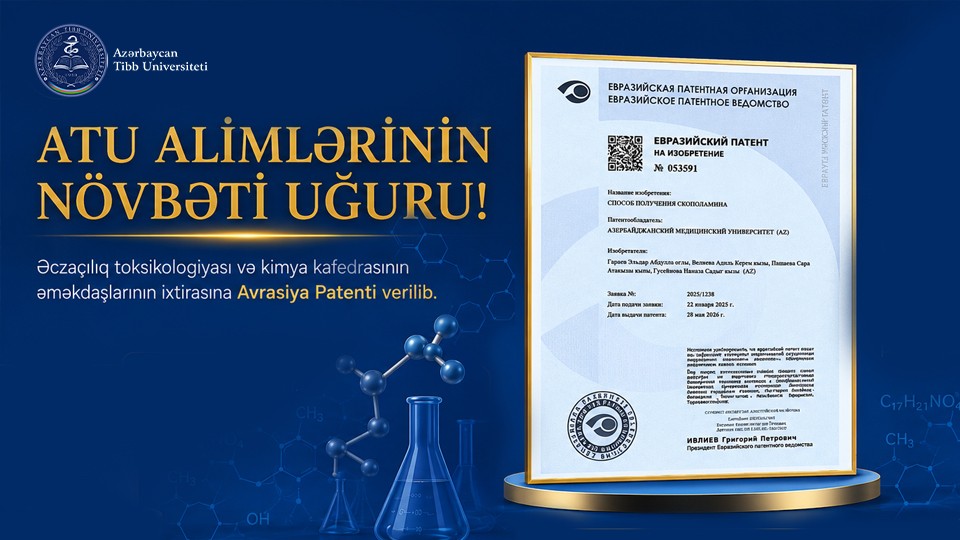

ATU-nun Əczaçılıq toksikologiyası və kimya kafedrası əməkdaşlarının ixtirasına Avrasiya Patenti verilib

17.06.2026 | 08:34